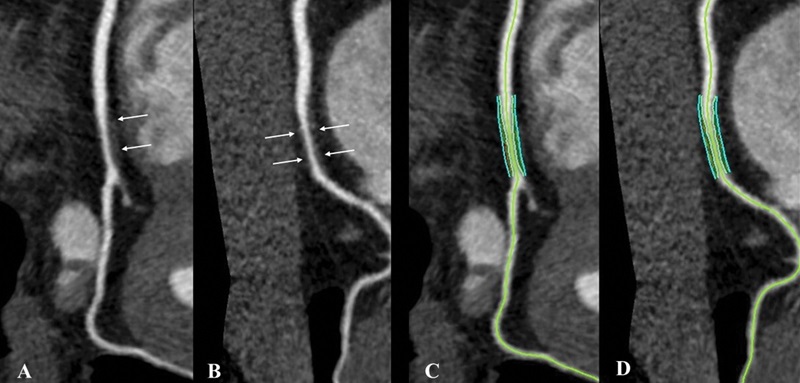

Noncalcified coronary plaque in an asymptomatic 52-year-old man living with HIV with a 10-year Framingham risk of 5%. Images show 256-section contrast-enhanced coronary CT angiography with electrocardiographic gating and curve reformat. A, B, CT scan shows a smooth noncalcified plaque in the right coronary artery (arrows) with 70%–80% stenosis. C, D, The right coronary artery plaque volume was 130 mm3 (cyan lines).

Boldeanu et al, Radiology 2021; 299:571–580 ©RSNA 2021